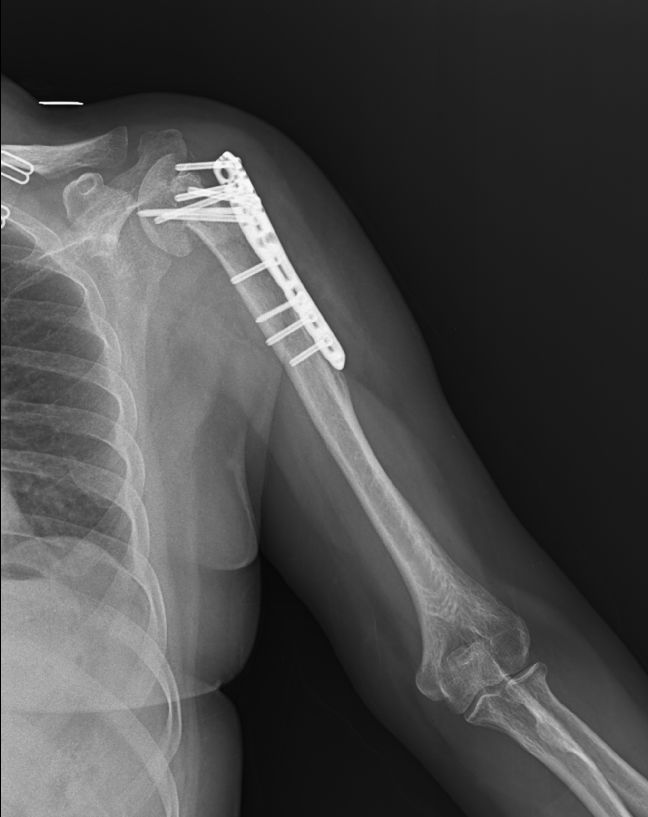

“一摔下去,左肩膀和胸背部鉆心般疼痛,疼得快暈過(guò)去了。”回想起當(dāng)日的情景,徐女士仍然心有余悸。救護(hù)車(chē)很快來(lái)了,將徐女士送往某醫(yī)院,檢查診斷為“左肱骨外科頸骨折”、“胸11椎體壓縮性骨折”、“骨盆骨折”,該院對(duì)徐女士受傷部位實(shí)行了鋼板螺釘固定等手術(shù)。

自那時(shí)以來(lái),徐女士一直積極接受康復(fù)理療。然而,效果并不如意,給徐女士生活帶來(lái)了極大的困擾,苦不堪言。徐女士說(shuō),雖然距離事故時(shí)隔近百日,但她左臂上端好像“廢”了,肩關(guān)節(jié)前屈后伸外展等各方向活動(dòng)均明顯受限,做每個(gè)動(dòng)作時(shí),都痛出了“表情包”。

“不能伸不能抬,稍微動(dòng)一下還痛得要命。”6月中旬,渴盼快快好起來(lái)的徐女士經(jīng)朋友介紹,來(lái)到嘉興嘉湖骨科醫(yī)院,尋求進(jìn)一步治療。